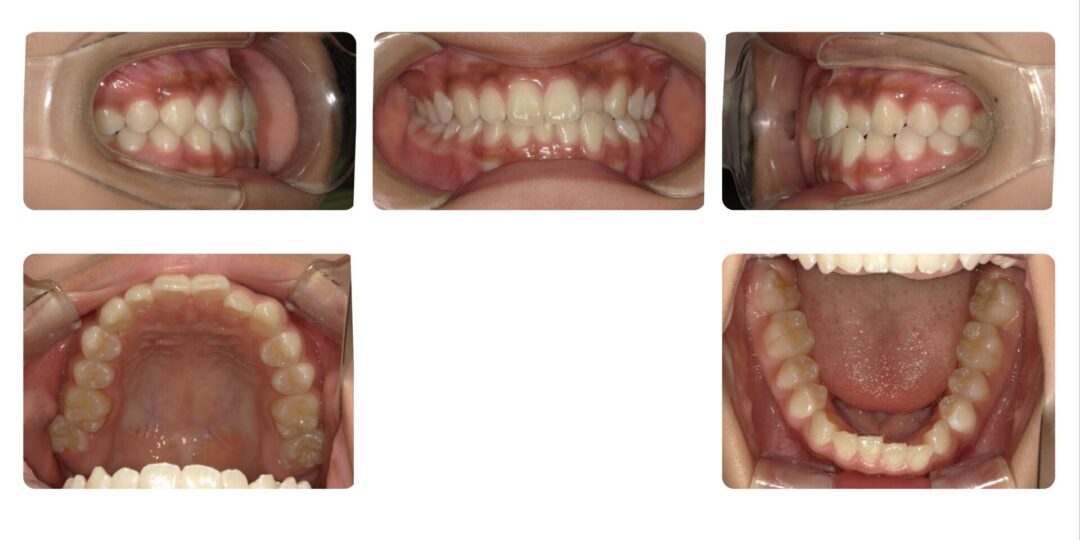

矯正治療前

中心がズレている

初診時12歳